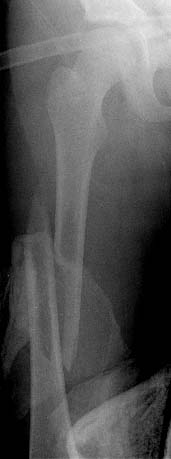

From: Kanlic, Enes M. M.D.

In deciding how to treat pediatric femur fractures the type of fracture and

weight of the patient are more important to be considered than the age.

"Problem" fractures (comminuted, long spiral, high sub or pertrochanteric,

supracondylar fx) do represent 43% of cases in Flynn, 2001 study, and 55% in

Heinrich,1994 study. For those fractures PERCUTANEOUS SUBMUSCULAR AND

EPIPERIOSTEAL BRIDGE PLATING is the best method.

Group of us (D. Smith, J. Anglen, S. Morgan, R. Pesantez, P.Cole) have done

more than 40 cases. Average OR time 103 minutes, x-ray time 105 seconds. No

infections or nonunions. All had excellent clinical result. Complications:

one temporary peroneal palsy, one valgus malalignment and one plate bending

after new injury (reduced closed and healed uneventfully).

Bridge plating provides elastic fixation for all type of fractures without

the need for bracing and casting, with excellent and reproducible results.

Plates are removed 6-12 month after injury.

In my opinion, stable fractures (transverse and short oblique shaft

fractures) should be treated with elastic intramedullary nails, what is even

less invasive than bridge plating.

Problems with other methods are:

1. Intramedullary elastic nailing: can not sufficiently stabilized "problem

fractures" (see above), in Flynn's study 70% of patients had to be put in

the cast; 9% did have complications.

2. External fixation: even after dynamization the refractering rate is to

high ( Minner, 2000: 21%; hardware support is simply to short). Bad scarring

and irritation - inflammation around pins are real problems (72% pins in

Miner's study were inflamed and required antibiotics). It is very difficult

if not impossible to treat supracondylar and subtrochanteric fractures with

this method.

3. Absolute stability osteosynthesis, compression plating: nonunion rate

is 10% in Fyodorov, 1999 study. To aggressive, "surgeon sensitive". 4. Locked, rigid intramedullary nailing: 5. Spica cast: for some authors is not desirable for patients heavier

than 50 lb (Stanitski, 1996).

I am attaching one of my cases.

Enes M. Kanlic, MD, PhD